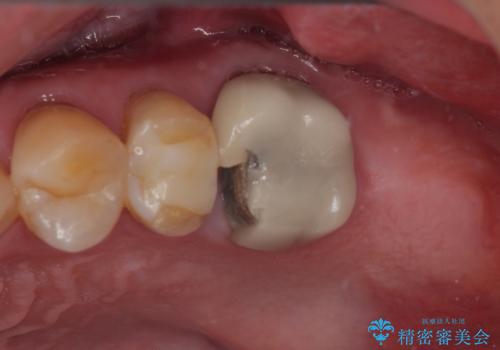

銀歯を外したい オールセラミッククラウン

担当医 有澤哲郎